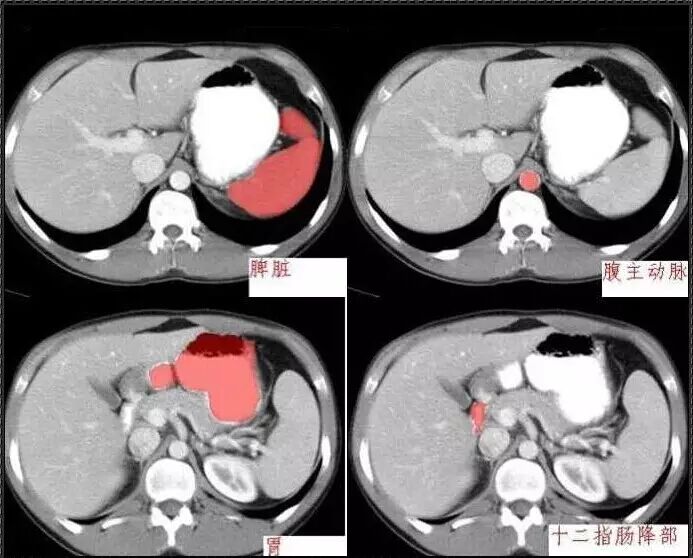

十分钟学会腹部CT解剖(多图)